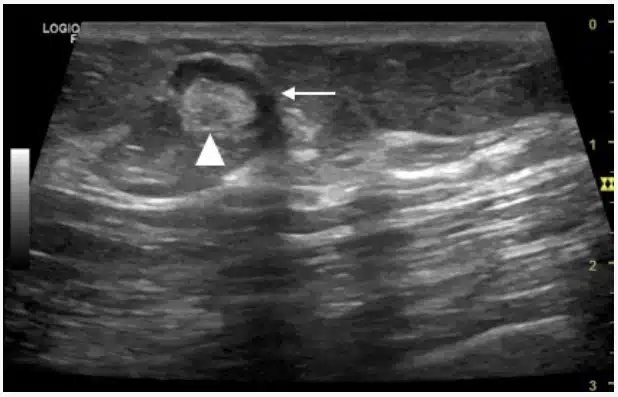

O ultrassom é frequentemente o primeiro exame solicitado devido à sua alta sensibilidade. O radiologista busca por alterações na arquitetura interna do linfonodo. Os sinais de malignidade no ultrassom incluem:

1. Perda do Hilo Ecogênico

O linfonodo normal tem uma parte central clara chamada hilo (gordura). Em casos de infiltração por câncer, esse centro desaparece, e o linfonodo torna-se uniformemente escuro (hipoecoico).

2. Formato Arredondado

Linfonodos saudáveis têm formato de feijão (ovalados). Quando se tornam malignos, tendem a ficar redondos. Médicos usam a relação entre o comprimento e o diâmetro; se a relação for menor que 2, a suspeita aumenta.

3. Vascularização Periférica

No Doppler, linfonodos reacionais mostram vasos sanguíneos entrando pelo centro (hilo). Já nos malignos, os vasos costumam surgir na periferia ou de forma caótica e desorganizada por todo o nódulo.

4. Microcalcificações e Necrose

A presença de pequenos pontos brancos (microcalcificações) ou áreas de liquefação (necrose) dentro do nódulo são fortes indícios de malignidade, especialmente em metástases de câncer de tireoide.